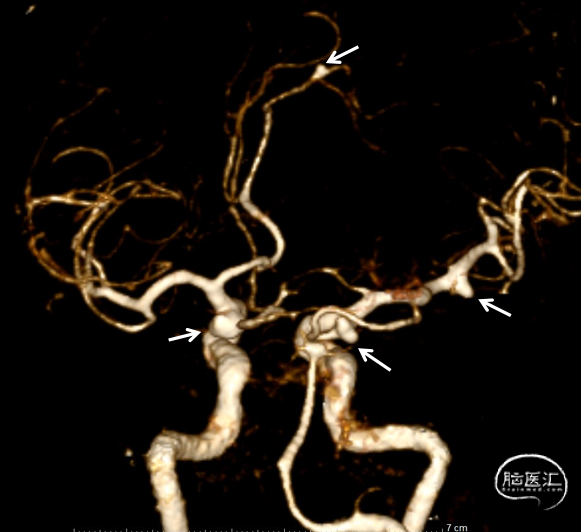

CTA示:双侧C7动脉瘤,LA3及RM1动脉瘤,双侧C7“镜像

患者静吸复合全麻造影示:左侧颈内动脉交通段可见约5.5mm×3.0mm大小动脉瘤,瘤颈宽2.7mm,右侧大脑中动脉可见2.0mm×2.1mm大小动脉瘤,瘤颈宽1.8mm。右侧颈内动脉交通段可见约6.3mm×5.8mm大小动脉瘤,瘤颈宽4.2mm,左侧大脑前动脉A3段可见约1.8mm×1.8mm大小动脉瘤,瘤颈宽1.3mm。右侧胚胎型大脑后动脉。

造影:左侧颈内动脉交通段动脉瘤支架辅助栓塞后改变,瘤体内无造影剂泻入,大脑中动脉及大脑前动脉走形正常,显影良好,左侧大脑前动脉A3段可见约2.0mm*1.5mm大小动脉瘤。右侧颈内动脉交通段可见约6.7mm*2.8mm大小动脉瘤,分叶状,瘤颈宽4.0mm,胚胎型大脑后动脉,右侧大脑中动脉M1段可见宽颈梭型动脉瘤,大小约3.9mm×4.6mm。

颅内“镜像”动脉瘤,系颅内两侧相对应部位发现的双侧对称出现的动脉瘤,为颅内多发动脉瘤的特殊类型。流行病学特征上女性多于男性,好发于颈内动脉系统,尤以大脑中动脉和后交通动脉常见,椎、基底动脉及其他部位少见。镜像动脉瘤位于大脑半球两侧,形态各异,手术处理难度高,入路选择和手术方案个体差异大。该患者双侧颈内动脉交通段均可见动脉瘤,第一次为左侧交通段动脉瘤破裂,为责任动脉瘤,优先予以处理,待病情平稳后,择期处理右侧镜像的交通段动脉瘤,同时该患者右侧大脑中动脉及左侧大脑前动脉远端各可见一形态不一的动脉瘤。